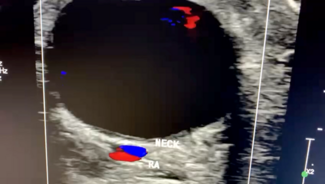

The authors present a 73-year-old female with history of rheumatic heart disease status post-mechanical mitral valve on warfarin, valvular atrial fibrillation, and alpha thalassemia who was admitted to an outside hospital with anterior...